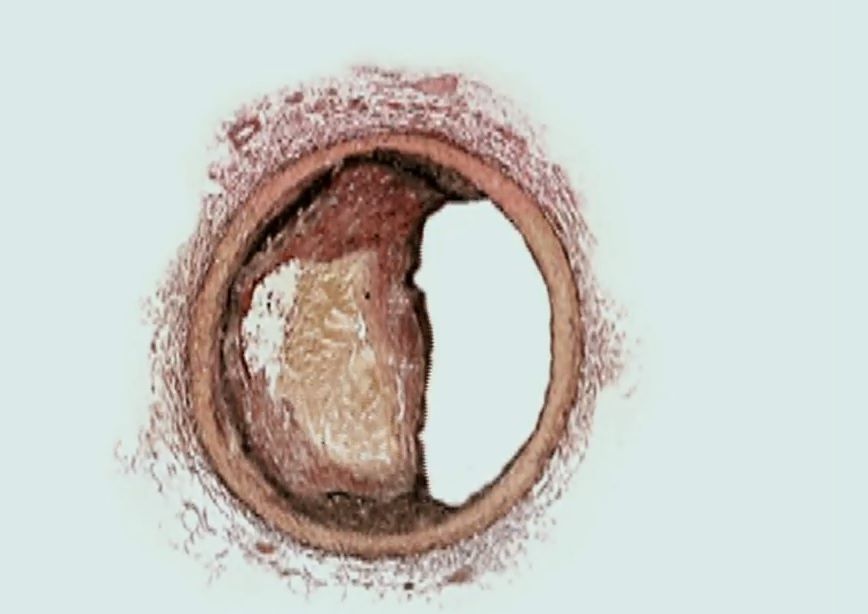

세포 노화를 유도하는 다양한 스트레스는 노화 세포 내 콜레스테롤 대사를 촉진함과 동시에, 콜레스테롤 유출 인자인 ABCA1의 세포 내 위치를 세포막에서 리소좀으로 변화시킨다. 리소좀에 위치한 ABCA1은 리소좀 콜레스테롤 유입 인자로 작용하며, 리소좀 내 콜레스테롤을 축적하고 리소좀 막 미세영역을 형성한다. 리소좀 막 미세영역은 영양-에너지 대사 경로의 주 조절 인자인 mTORC1의 활성을 강화하고, 염증 유발 분비 인자의 생성 촉진을 통해 만성 염증 및 노화를 일으킨다. 그림제공=서울대